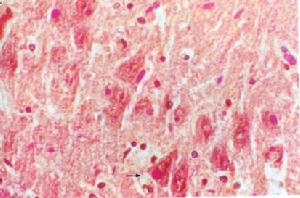

(1)光鏡下腎小球增大,細胞成分增多,血管襻肥大,內皮細胞腫脹,系膜細胞及系膜基質增生,毛細血管有不同程度的阻塞。此外常伴有滲出性炎症,可見中性粒細胞浸潤。由於增生、滲出的程度不同,輕者僅有部分系膜細胞增生;重者內皮細胞也增生,並可部分甚至全部阻塞毛細血管襻;更嚴重者形成新月體。臨床表現為急進過程者則有廣泛新月體形成。

(2)電鏡檢查:於上皮下可見本病典型的駝峰改變(即上皮下有細顆粒的電子緻密物沉積)。駝峰一般於病後6~8周消失。

(3)免疫螢光檢查:沿毛細血管襻及系膜區可見瀰漫顆粒狀的IgG、C3、備解素及纖維蛋白相關抗原沉著,偶見IgM、IgA、C1q、C4等沉著。本病腎活檢的指征是:①少尿1周以上或進行性尿量減少伴腎功能惡化,有急進性腎炎的可能者;②起病後2~3個月病情無好轉,仍有高血壓、持續的低補體血症者;③急性腎炎綜合徵伴腎病綜合徵者。鑑別診斷1.全身感染性發熱疾病各種感染引起發熱時,腎血流量及腎小球通透性可增加,也可出現一過性蛋白尿,此種改變於高熱、感染的早期發生,退熱後尿液即恢復正常,無急性腎炎綜合徵的其他症狀。